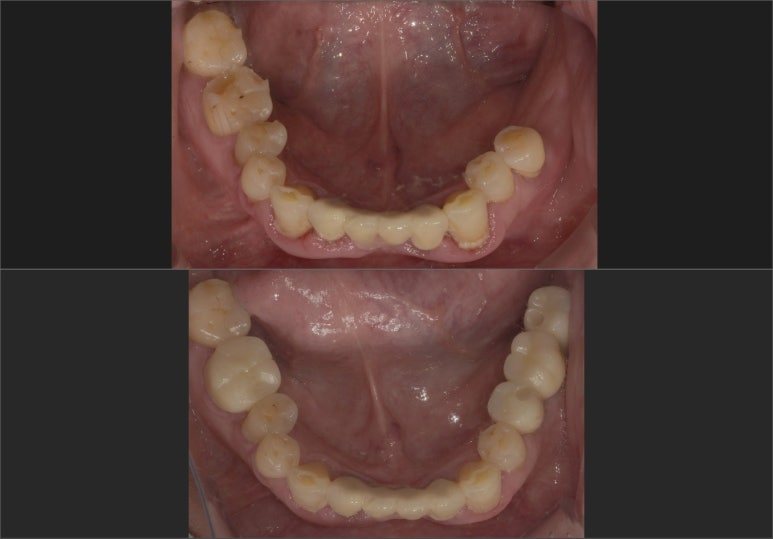

임플란트브릿지 치료전후

(위) 치료전 2023-03-24

(아래) 치료후 2023-06-29

수술 전후 모습을 한번 비교해볼까요?

상실되었던 치아가 임플란트 식립으로 빼곡하게 채워진 모습을 보실 수 있습니다.